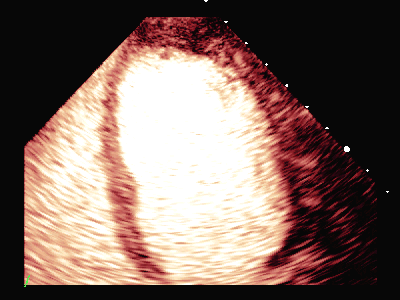

MCE:

动态图(4)负荷状态左室长轴

平板负荷量达89%时,该时患者心率157次/分,出现短阵性室性心动过速,即刻超声造影检查显示:负荷后左室前间隔中段、室间隔心尖段、侧壁中段、心尖段、下壁心尖段、前壁心尖段及心尖帽运动减弱。室间隔心尖段及心尖帽心肌灌注稀疏。

患者休息后检查:左室壁未见明确节段性运动异常,左室各节段心肌灌注充盈良好。